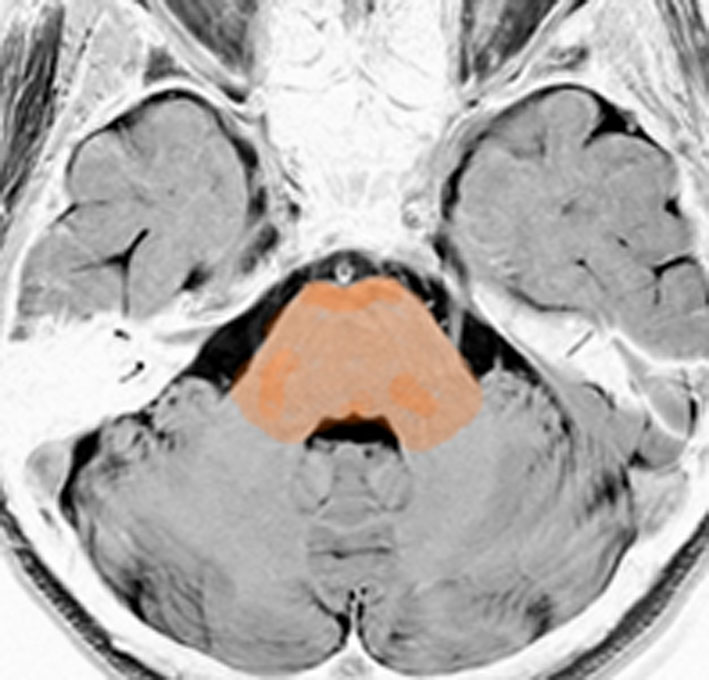

脳幹部の解剖図

- 脳の底面からしか見えないのでいろいろな角度から見ています

これは脳の中心部を縦切りにした写真です。脳幹部は上から順に,中脳 midbrain (黄色),橋 pons(オレンジ),延髄 medulla oblongata(ピンク)と呼ばれます。